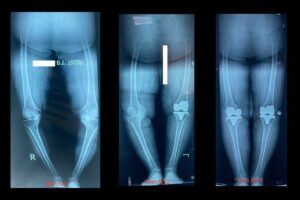

Операції на коліні: артроскопія, зв’язки та ендопротези

Ми лікуємо травми та артроз коліна артроскопічно або протезуванням, використовуючи індивідуальні імпланти й сучасні протоколи реабілітації.